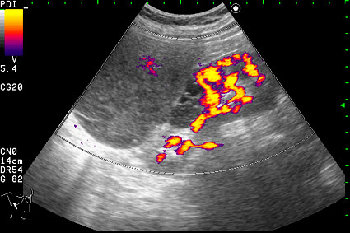

Образование в режиме энергетического доплера.

Нет, это кистоподобное образование, связанное с почкой.

Необычнвя картинка. В голову приходят самые "сумашедшие" предположения (в т.ч. малигнизация кисты, но нет кровотока, нагноившаяся киста, но нет реакции ее стенки; киста с густым содержимым, но отчего оно так загустело?). Просветите нас, пожалуйста.

Почечно-клеточный рак правой почки, кистозная форма.

Но только по густому содержимому кистозного компонента. Стенка тонкая, кровоток не прокрашивается (единичный мелкий срез сосуда в центре образования больше похож на артефакт, а м.б. им и является).

Если бы в этом случае и содержимое было бы более "жидким", вероятность постановки правильного диагноза была бы минимальной.